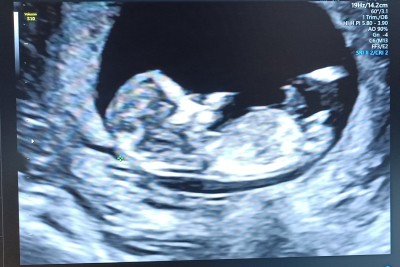

Cinsiyet tahmini yapar mısınız arkadaşlar şimdiden teşekkürler

Yuvarlak kese kız fasulye gibi olana erkek derler. Rabbim sağlıklı versin inşallah <3

Bilmiyorum nedense erkek hissetim öğrenince yaz birde kaç haftalık

Erkek gibi ama bilemedim öğrenince yaz bakalım doğru mi tahmin etmişiz

Doktor erkek gibi ama kesin diyemem dedi ikili tarama testi yapıldı bugün tahminde bulundu pipisi gözüküyor dedi tabi yanlış gormediyse

Kız bebek bnce bu kese tipinden öyle gorunuyo

Doktor erkek dedi ama kesin diyemem dedi 12 haftalığım

Doktorun demesine bakma:D ben diyorum kesin kız

Erkek gibi geldi bana hayırlısıyla kucağına alırsın inşallah 12 haftalık mi

Evet canım 12 haftalık doktor erkeğe benziyo ama kesin diyemem dedi pipisi gözüküyor dedi (⁠•⁠‿⁠•⁠)